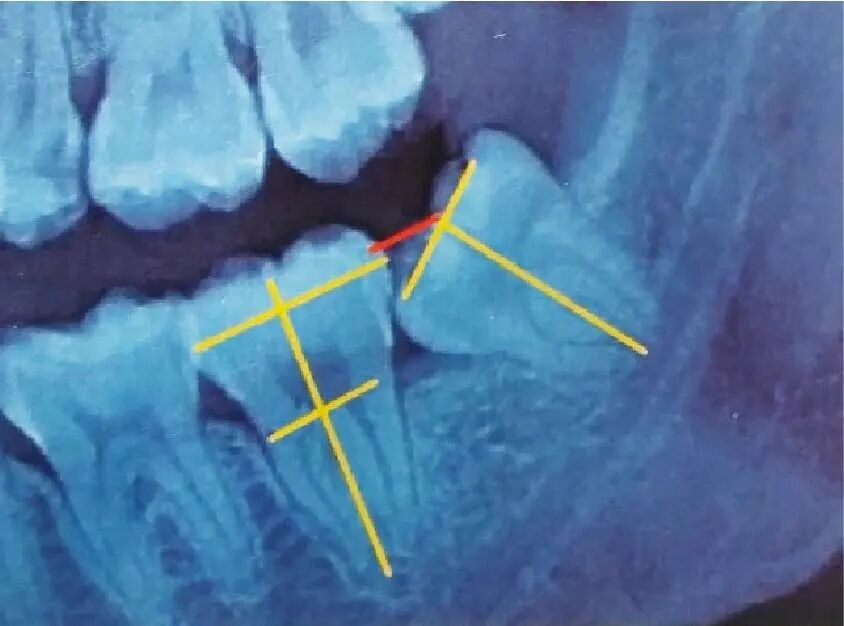

3)

下颌近中倾斜

低位阻生

阻生齿-05.jpg

髓室底到根尖部分为低位(上颌智齿则相反)。